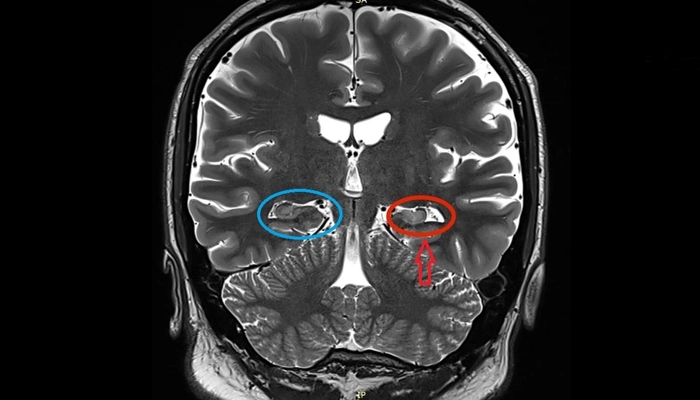

Hình ảnh MRI teo hồi hải mã trong động kinh thùy thái dương

Các vùng thường bị ảnh hưởng gồm hồi hải mã và hệ viền, là những khu vực đóng vai trò quan trọng trong kiểm soát cảm xúc và trí nhớ. Khi các vùng này bị tổn thương, tín hiệu thần kinh trở nên rối loạn và dễ lan sang các vùng não khác.

Tổn thương hồi hải mã: liên quan chặt chẽ đến trí nhớ và khởi phát cơn